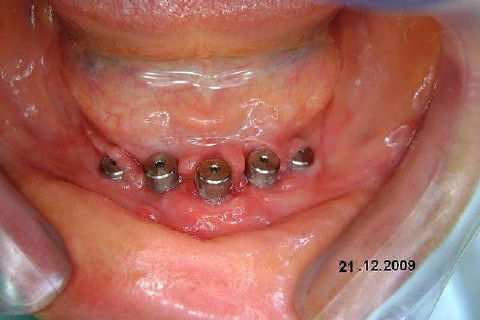

Apesar da boa adaptação e estética satisfatória, a principal queixa da paciente era a instabilidade da prótese inferior, como sempre ocorre nestes casos...atrofia do rebordo alveolar e perda da função mastigatória.